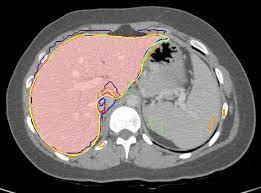

Gastro-Intestinal Tract cancer is considered a fatal malignant condition of the organs in the GI tract. Due to its fatality, there is an urgent need for medical image segmentation techniques to segment organs to reduce the treatment time and enhance the treatment. Traditional segmentation techniques rely upon handcrafted features and are computationally expensive and inefficient. Vision Transformers have gained immense popularity in many image classification and segmentation tasks. To address this problem from a transformers' perspective, we introduced a hybrid CNN-transformer architecture to segment the different organs from an image. The proposed solution is robust, scalable, and computationally efficient, with a Dice and Jaccard coefficient of 0.79 and 0.72, respectively. The proposed solution also depicts the essence of deep learning-based automation to improve the effectiveness of the treatment

翻译:胃内肠道癌被认为是GI大片器官致命恶性病,由于其致命性,迫切需要医疗图象分解技术,以便分器官减少治疗时间,加强治疗;传统分解技术依靠手工制作的特征,计算成本低,效率低;许多图像分类和分解任务中,视觉变形器受到极大欢迎。从变压器的角度来看,为了解决这一问题,我们引入了混合型CNN-传输结构,将不同器官与图像分割开来。 拟议的解决办法是稳健、可缩放和计算效率高的,Dice和Jacccard系数分别为0.79和0.72。 拟议的解决办法还描述了深层学习自动化的本质,以提高治疗的效果。